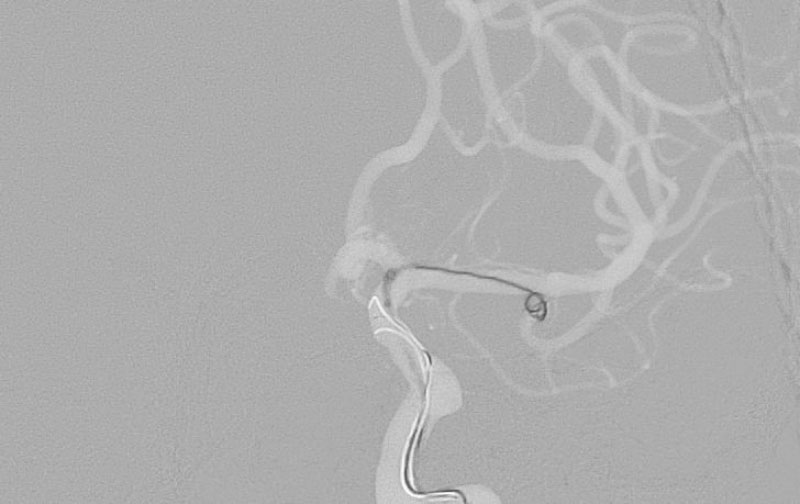

No.1596 手術後